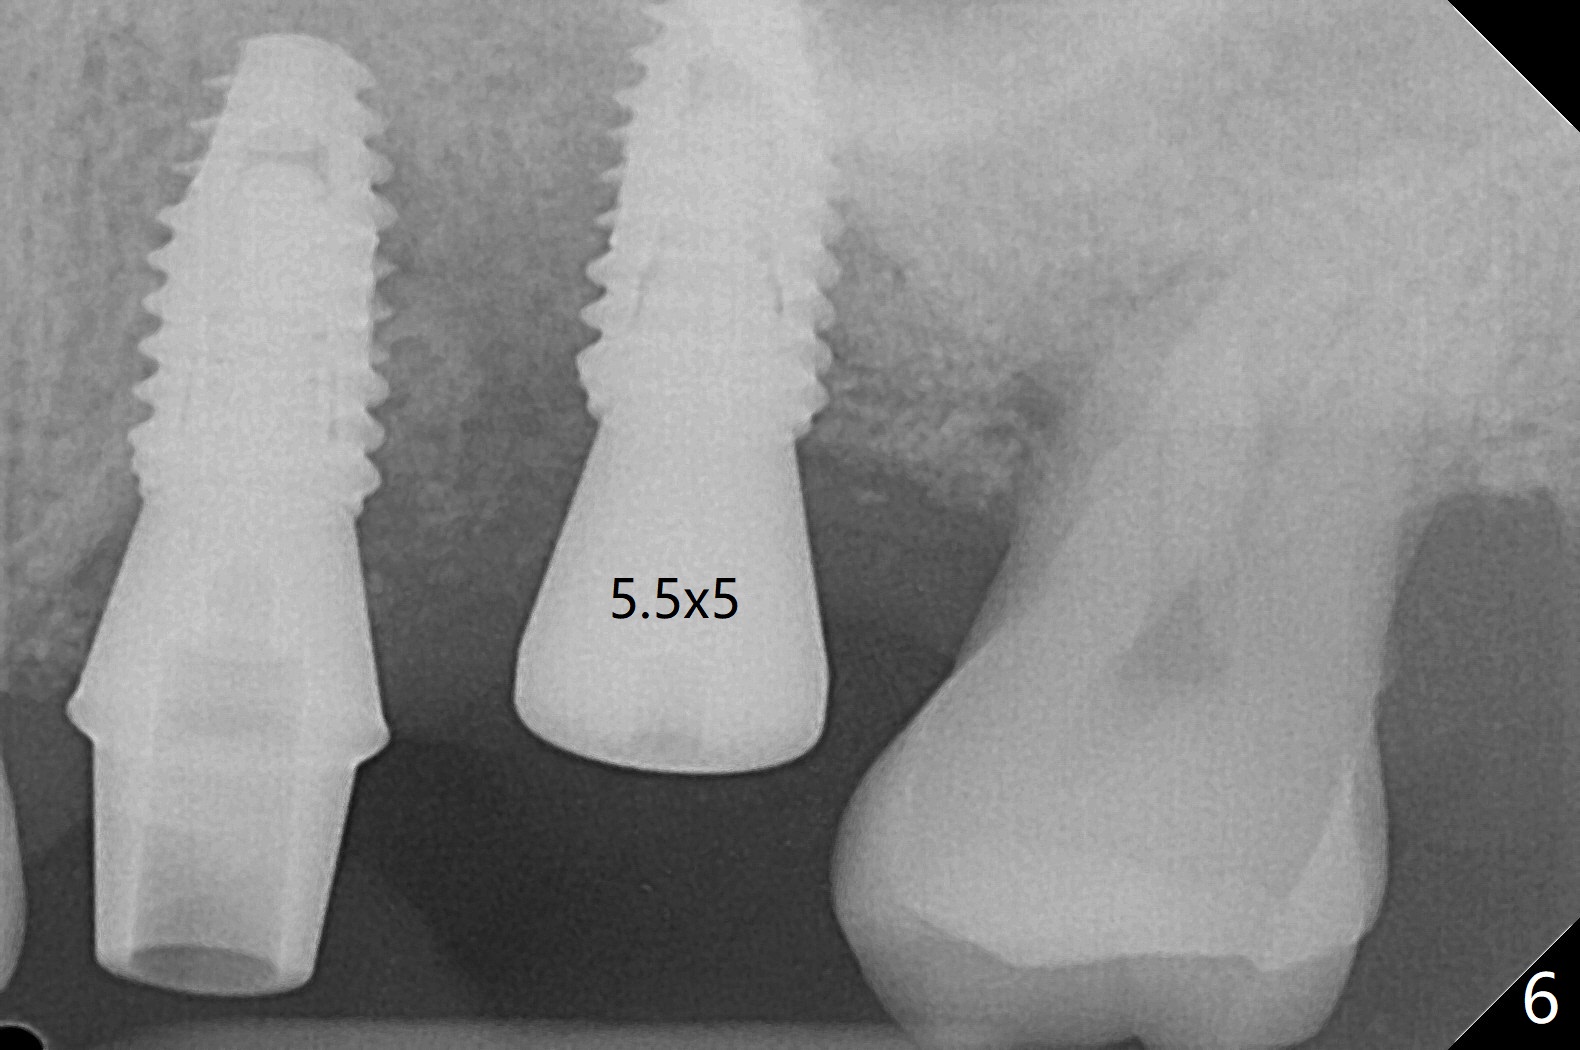

左上六植牙第三次失败后五个月,牙槽嵴宽度尚可,切开后放置导板,3.2乘19毫米园钻头好像接近上颌窦底板(图一),但是粘性骨块和4乘10毫米报废植体就不能进入上颌窦(图二),最后不得不使用3毫米Bicon骨凿,之后同一个报废植体就似乎进入上颌窦(图三),4.5乘8.5毫米正式植体植入深度和稳定性均正常(图四),腭侧植体稍微暴露,放置愈合螺丝后,放置骨粉和PRF膜,缝合,左上5植体放置5.7x4.5(4)毫米基台,固定牙周敷料。术后5.5个月植体好像整合(图五),缺牙间隙特别小,5临时牙冠(P)必须取出才能切开暴露植体,放置5.5x5毫米愈合基台(图六)。伤口愈合后,必须做渐进性负荷,之后做简单局部矫正,推7往远中,6缺失3年,7往近中倾斜移位。两周后牙周敷料脱落,伤口愈合,放置修复基台,故意将基台平面朝远中,足够空间制作临时牙冠(图七)。调整基台长度(比较图七,八)。制作连体牙冠(5,6),有意提高5牙冠高度,使左上7不与对合牙接触,有利于远中移位(图九)。也要在对侧提高咬合(图十)。局部矫正一个月后,磨去右侧咬合垫和磨短左上5,6临时牙冠,前牙还不能完全接触(图十一)。1-2星期前牙开合自行消失,取模做左上5,6牙冠。局部矫正似乎使左上7远中移位大约3毫米(比较图十二,十三)。粘固拧紧后(20 Ncm)14号牙牙冠咬合增高,拍摄根尖片(图十三),两个基台好像仍然完全就位,然后调整咬合。